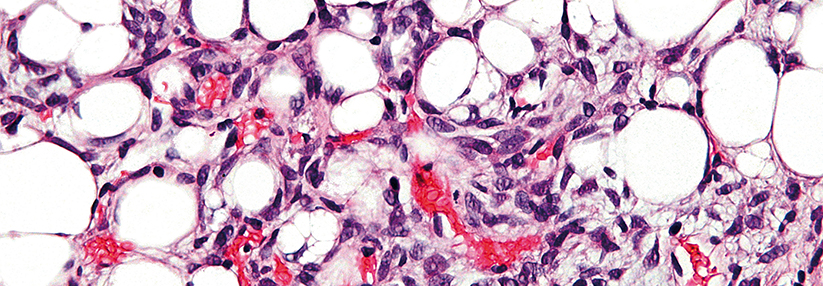

Den Tumor nicht mehr systemisch behandeln, sondern Zytostatikum, Checkpoint-Inhibitor oder Adenovirus-Vektoren direkt ins Bronchialkarzinom applizieren: Beim Nicht-Kleinzeller werden solche lokalen Therapiestrategien derzeit geprüft.

Das vergangene Jahrzehnt hat erhebliche Fortschritte in der Behandlung des nicht-kleinzelligen Bronchialkarzinoms (NSCLC) gebracht, nicht zuletzt durch die Entwicklung der Checkpoint-Inhibitoren. Doch auf sie spricht nur etwa jeder fünfte Erkrankte an. Außerdem besteht bei ihnen das spezielle Risiko von teils deletären immunologisch bedingten Nebenwirkungen. Dazu trägt auch die sys­temische Applikation bei.